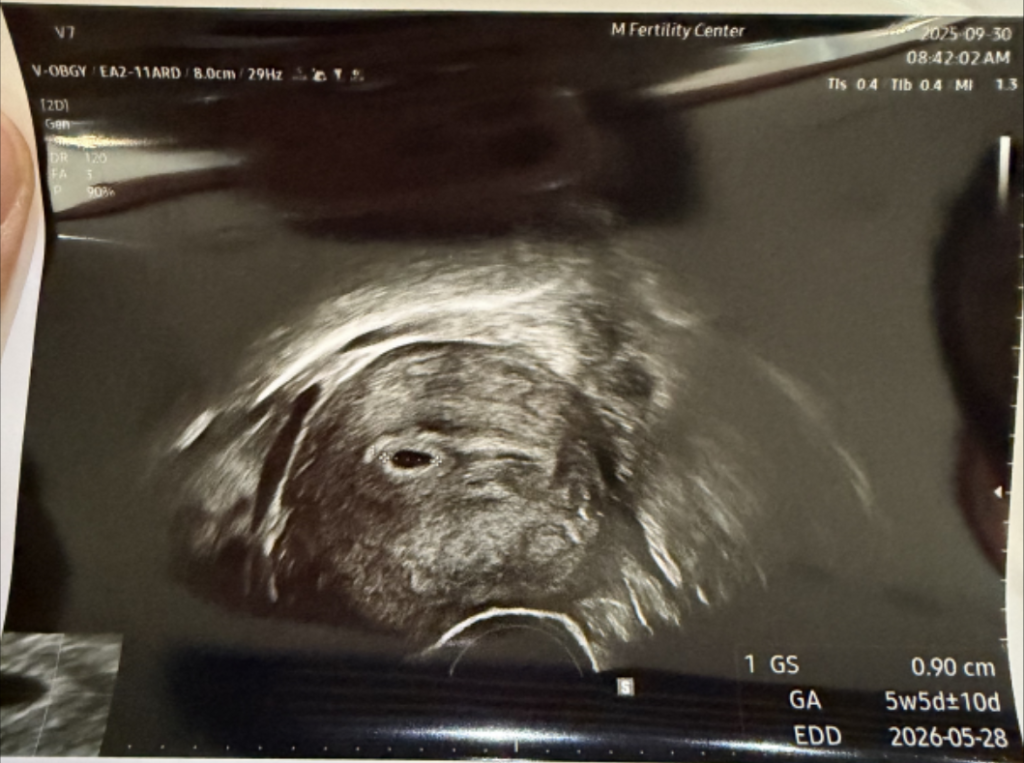

임신 5주 5일 차 아기집(GS 0.90cm) 초음파 사진

임신 5주 차(정확히는 5주 5일), 콩알만 한 0.9cm 아기집을 처음 확인한 날

딱 임신 5주 차가 되는 날. 이날은 근무 때문에 아내와 함께 병원을 가지는 못했다. 전해 들은 얘기로는 임신 주수에 비해 아기는 좀 컸다고 한다. 그런데 뭐가 큰 건지는 잘 모르겠다. 집에 돌아와 초음파 사진을 봤는데 정말 콩알만 했다. 1cm도 되지 않는 그야말로 작고 소중한 존재가 엄마의 뱃속에 자리를 만들어냈다.

아기집을 확인한 결과 단태아 판정을 받았다. 쌍둥이가 아닌 것에 다행이라고 느끼면서 한편으로는 아이가 태어난 뒤로는 또 아이를 가지기가 힘들 텐데 형제가 없을 수 있다는 것이 걱정되기도 했다. 아내는 쌍둥이였으면 더 좋았겠다는 얘기를 했다. 정답은 없고 임신과 출산은 우리가 원하는 대로 흘러가지 않았기에 이제부터는 그 어떤 결과라도 겸허히 받아들여야겠다고 생각했다.